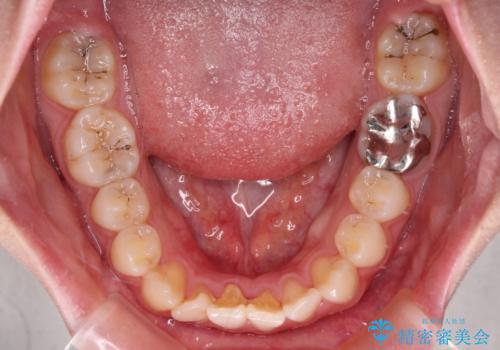

- 左右の八重歯を気にして来院された患者様です。

歯列としてはインビザラインでもワイヤー矯正でも対応できるものでしたが、インビザラインによる治療を希望されていました。

上顎の八重歯改善にインビザラインでは時間のかかってしまう可能性があり、更には口元が治療前よりも突出してしまう可能性があったため、補助装置により八重歯を事前に引き込んでおくことで、インビザラインによる治療をスムーズに行えるように計画しました。